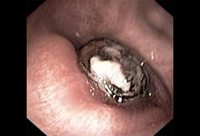

Foreign body aspiration

Loquat seed completely occluding the bronchus intermedius

From the collection of Dr Septimiu Murgu and Dr Henri Colt; used with permission